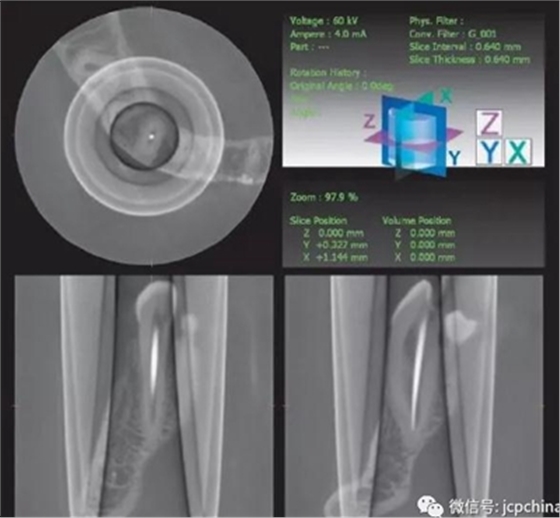

(5)環(huán)形偽影

探測(cè)板上的缺陷導(dǎo)致環(huán)形影像。環(huán)形偽影常常圍繞著旋轉(zhuǎn)中心。